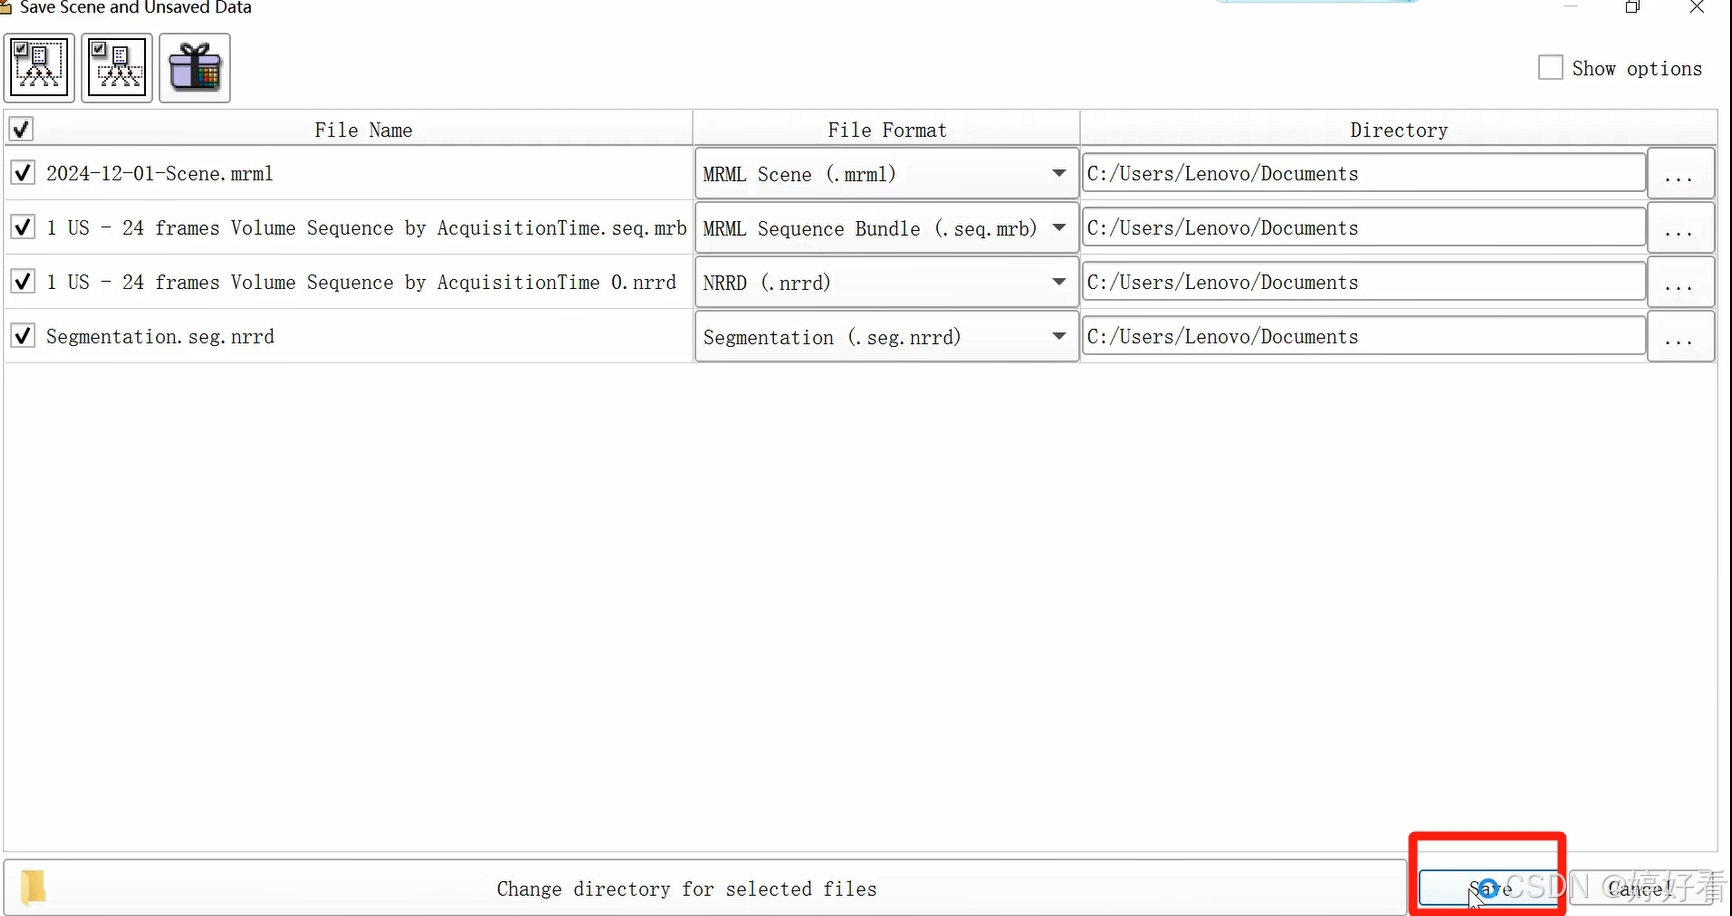

3、 保存

点击“Save”,弹出的对话框包含4个文件,其中2个是分割前的原始文件,另外2个是分割后的文件。

将对话框放大,可以修改单个文件的保存路径。

也可以同时修改4个文件的保存路径。

最后,选择保存。